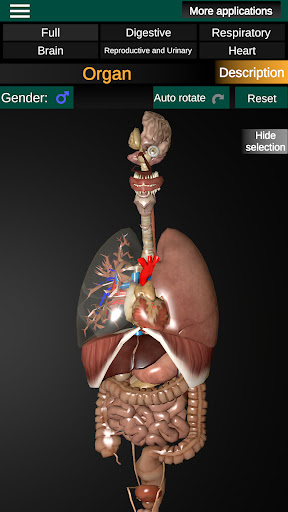

Toont een 3D-anatomisch model van de belangrijkste organen van het menselijk lichaam en een beschrijving van elk orgaan.

Wat zit er in de app?

* Spijsverteringsstelsel, inclusief de maag, dunne darm, dikke darm, en een animatie van dit systeem.

* Ademhalingssysteem, inclusief de luchtpijp, bronchiën, longen en een animatie van dit systeem.

* Hart, dat de atria, ventrikels, aorta en een animatie van dit orgel omvat.

* Gemakkelijk te openen en te navigeren (zoom, 3D-rotatie).

* Verberg of toon informatie.

* Beschrijvingen van elk orgel.